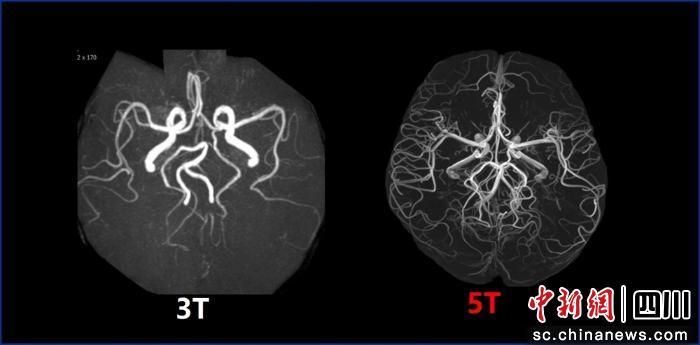

此前,临床主流磁共振场强为1.5T和3.0T;国际上7.0T磁共振虽场强更高,但仅能实现头颅及膝关节平扫,适用范围较窄。此次投用的5.0T磁共振,相比3.0T成像清晰度大幅提升,可精准识别1毫米乃至部分部位0.5毫米以下的微小病变或早期肿瘤,为疾病早诊早治提供关键支撑;相较于7.0T,其适用场景更全面,可覆盖全身成像,为中枢神经系统、心血管系统、腹盆腔等多部位诊断提供高清影像依据。